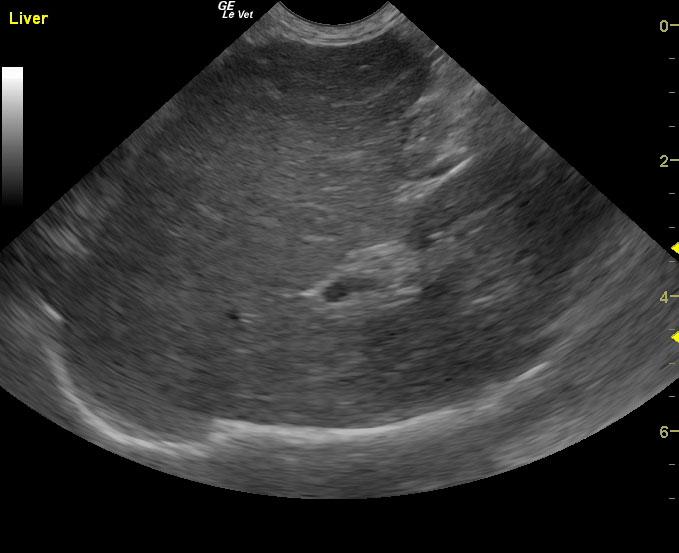

A 15-year-old neutered male DSH cat was presented for evaluation of polyphagia, weight loss, and severe splenomegaly. Abnormalities on CBC and serum biochemistry included leukocytosis, mild hypoalbuminemia, and an elevated BUN 42.